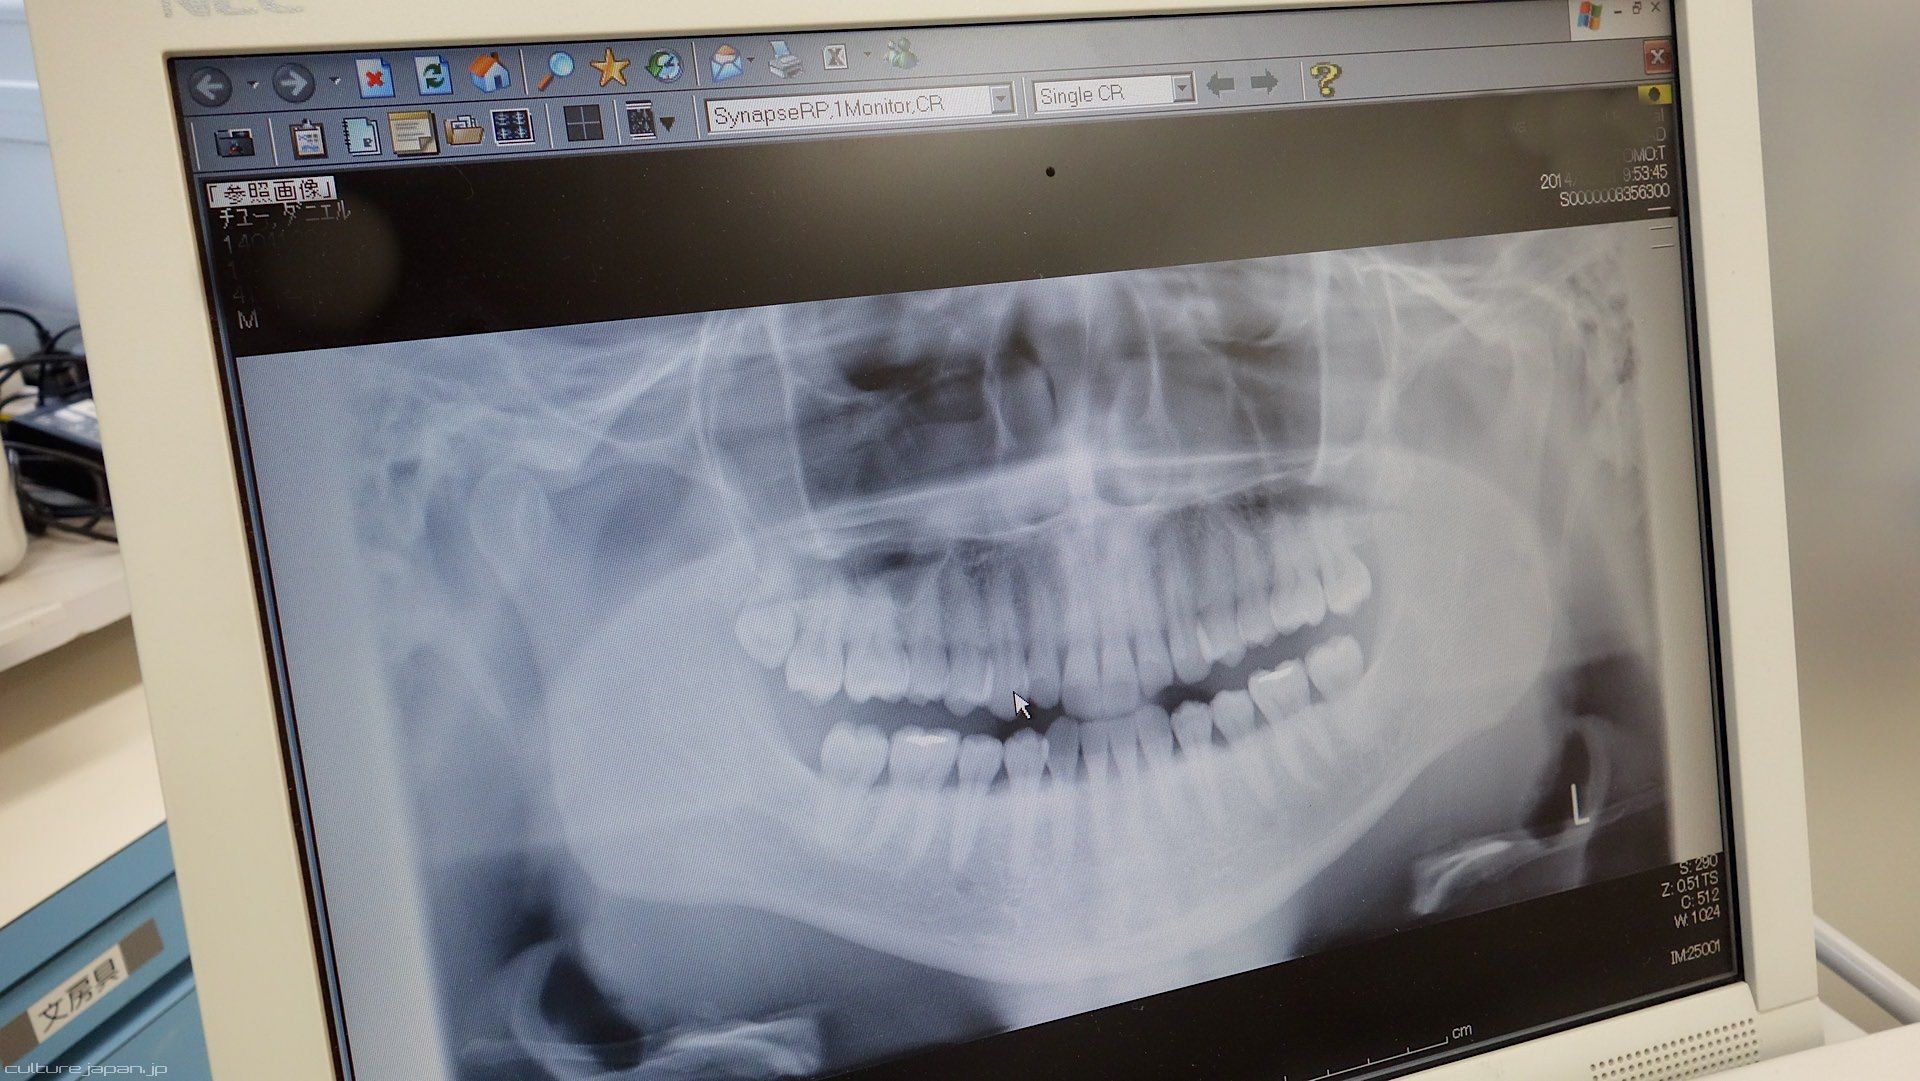

This is a photo of the x-ray that they took at the hospital - you can see the last wisdom tooth in the upper left of the photo - get it out!